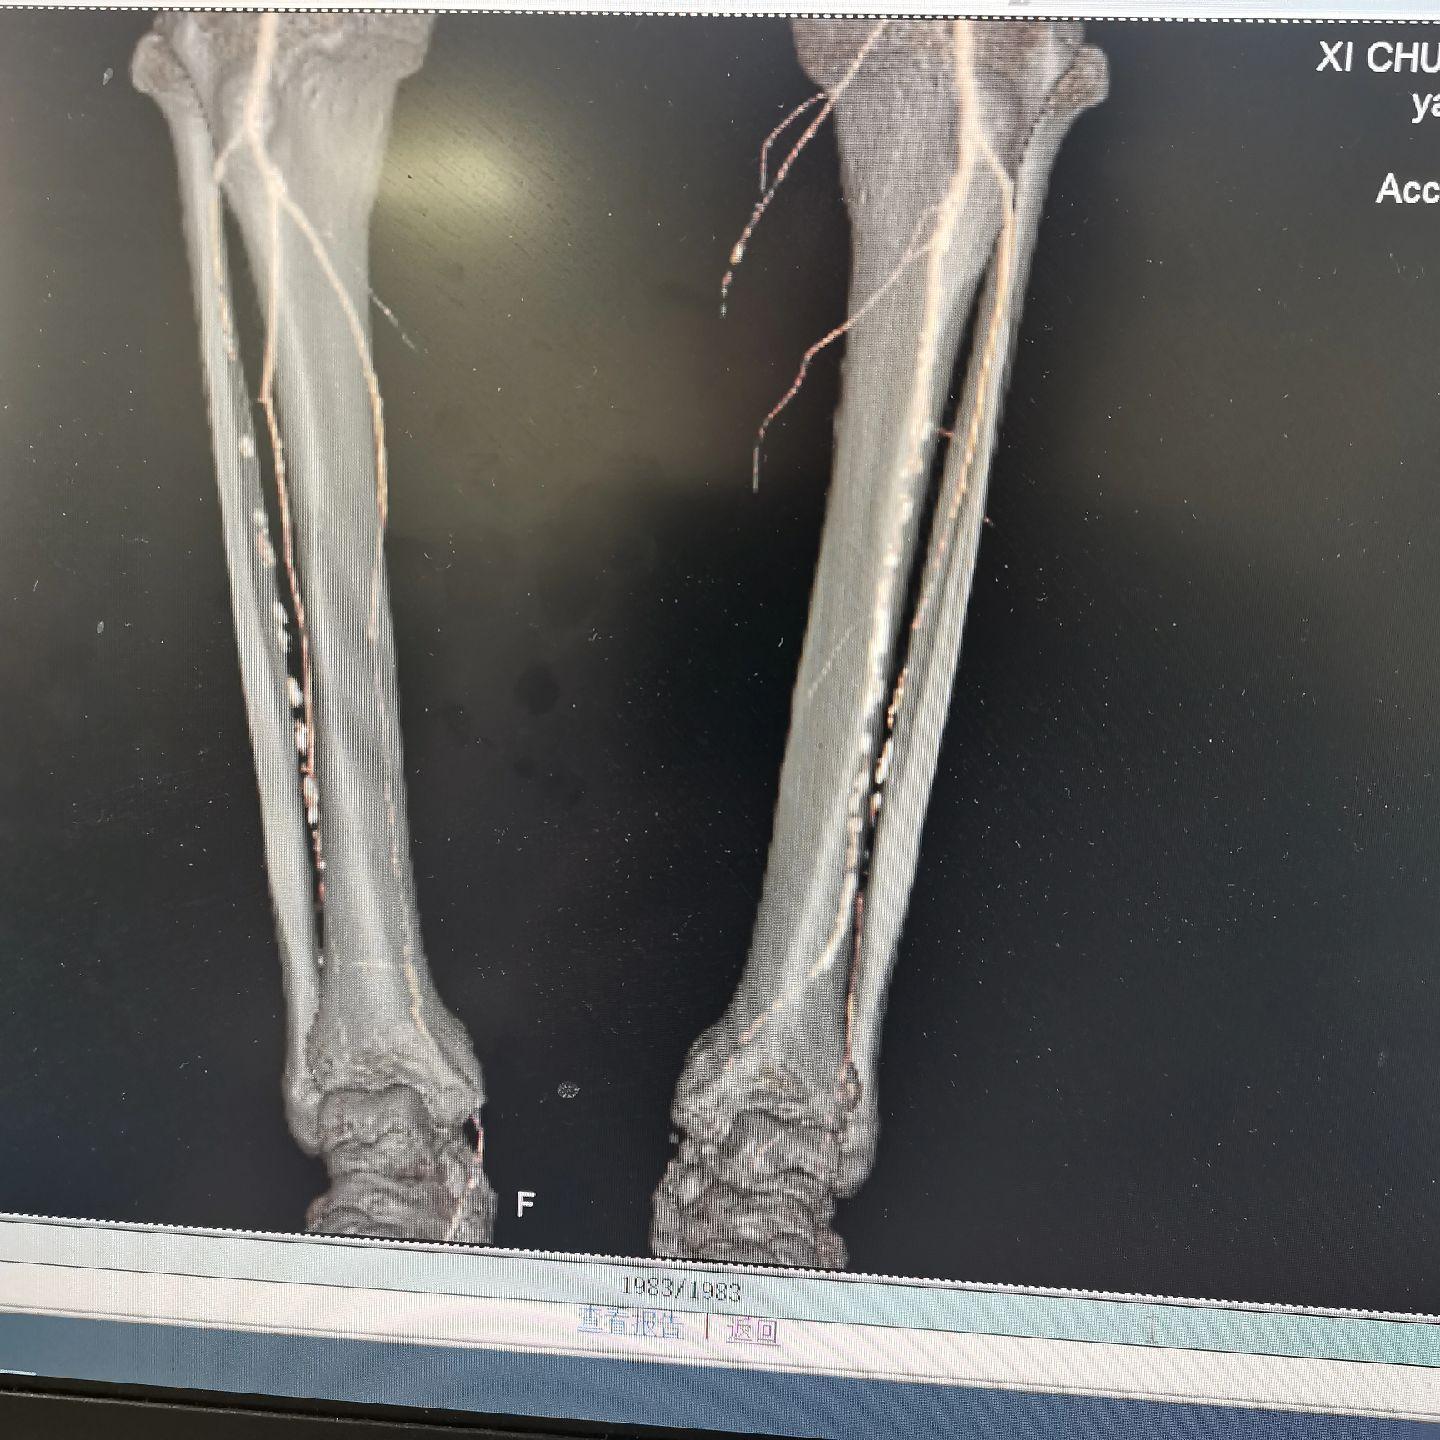

一例糖尿病足,左下肢溃烂不愈合,静息痛严重影响生活。开通闭塞段,行球囊扩张!即刻恢复血流,足背红润皮温升高,疼痛消失!